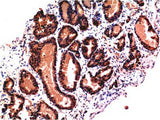

Applications IHC-p

IHC 1:100-200